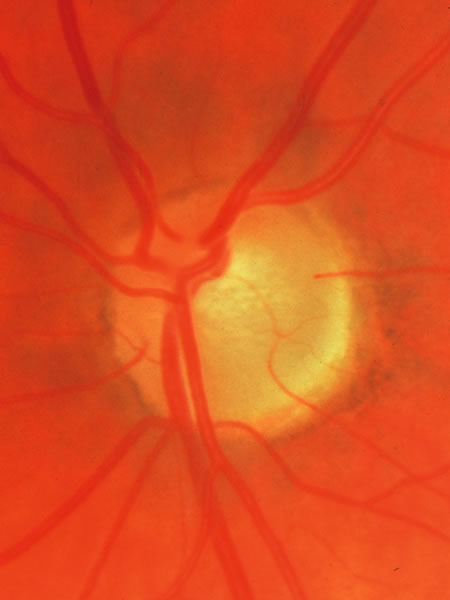

The approximately 1 to 1.5 million axons that form the optic nerve arise from the retinal ganglion cells and course toward the optic disc in a well-known pattern (Fig. 1). From the nasal retina the fibers take a straight course toward the disc. Axons originating temporal to the fovea arc around the macula to enter the upper and lower poles of the optic nerve head. The macula fibers pass directly to the temporal quadrant of the disc in the papillomacular bundle.

Fig. 1. Fundus photograph shows the normal pattern of the retinal nerve fiber layer. (Courtesy of P. Juhani Airaksinen, MD).